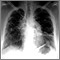

- Chest x-ray to see if the lungs are involved or lymph nodes are enlarged

To diagnose this condition, a biopsy is needed. A biopsy of the lung using bronchoscopy is usually done. Biopsies of other body tissues may also be done.